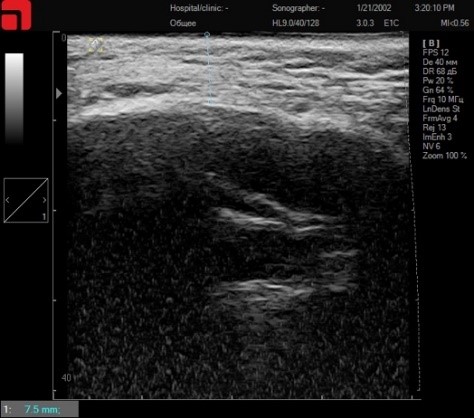

В скуловой области необходимо определить глубину залегания костной дуги (Arcus zygomaticus), чтобы не травмировать надкостницу и сосудисто-нервные пучки, выходящие на этой глубине (Рис.4.). При необходимости – не заходить на эту область манипулой соответствующей глубины. В данном случае можно работать манипулами 3 мм M7 и 4,5 мм D4 до верхнего края скуловой дуги, так как надкостница находится на глубине 7,5 мм.

Сканирование скуловой дуги

Рис. 4. Сканирование скуловой дуги.